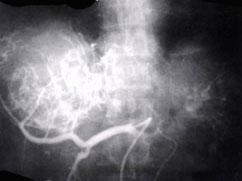

最佳的小肝癌定位诊断方法是 ( )A、选择性动脉造影B、MRIC、CT检查D、X线钡餐E、B超

选项 A、选择性动脉造影 B、MRI C、CT检查 D、X线钡餐 E、B超

答案 A